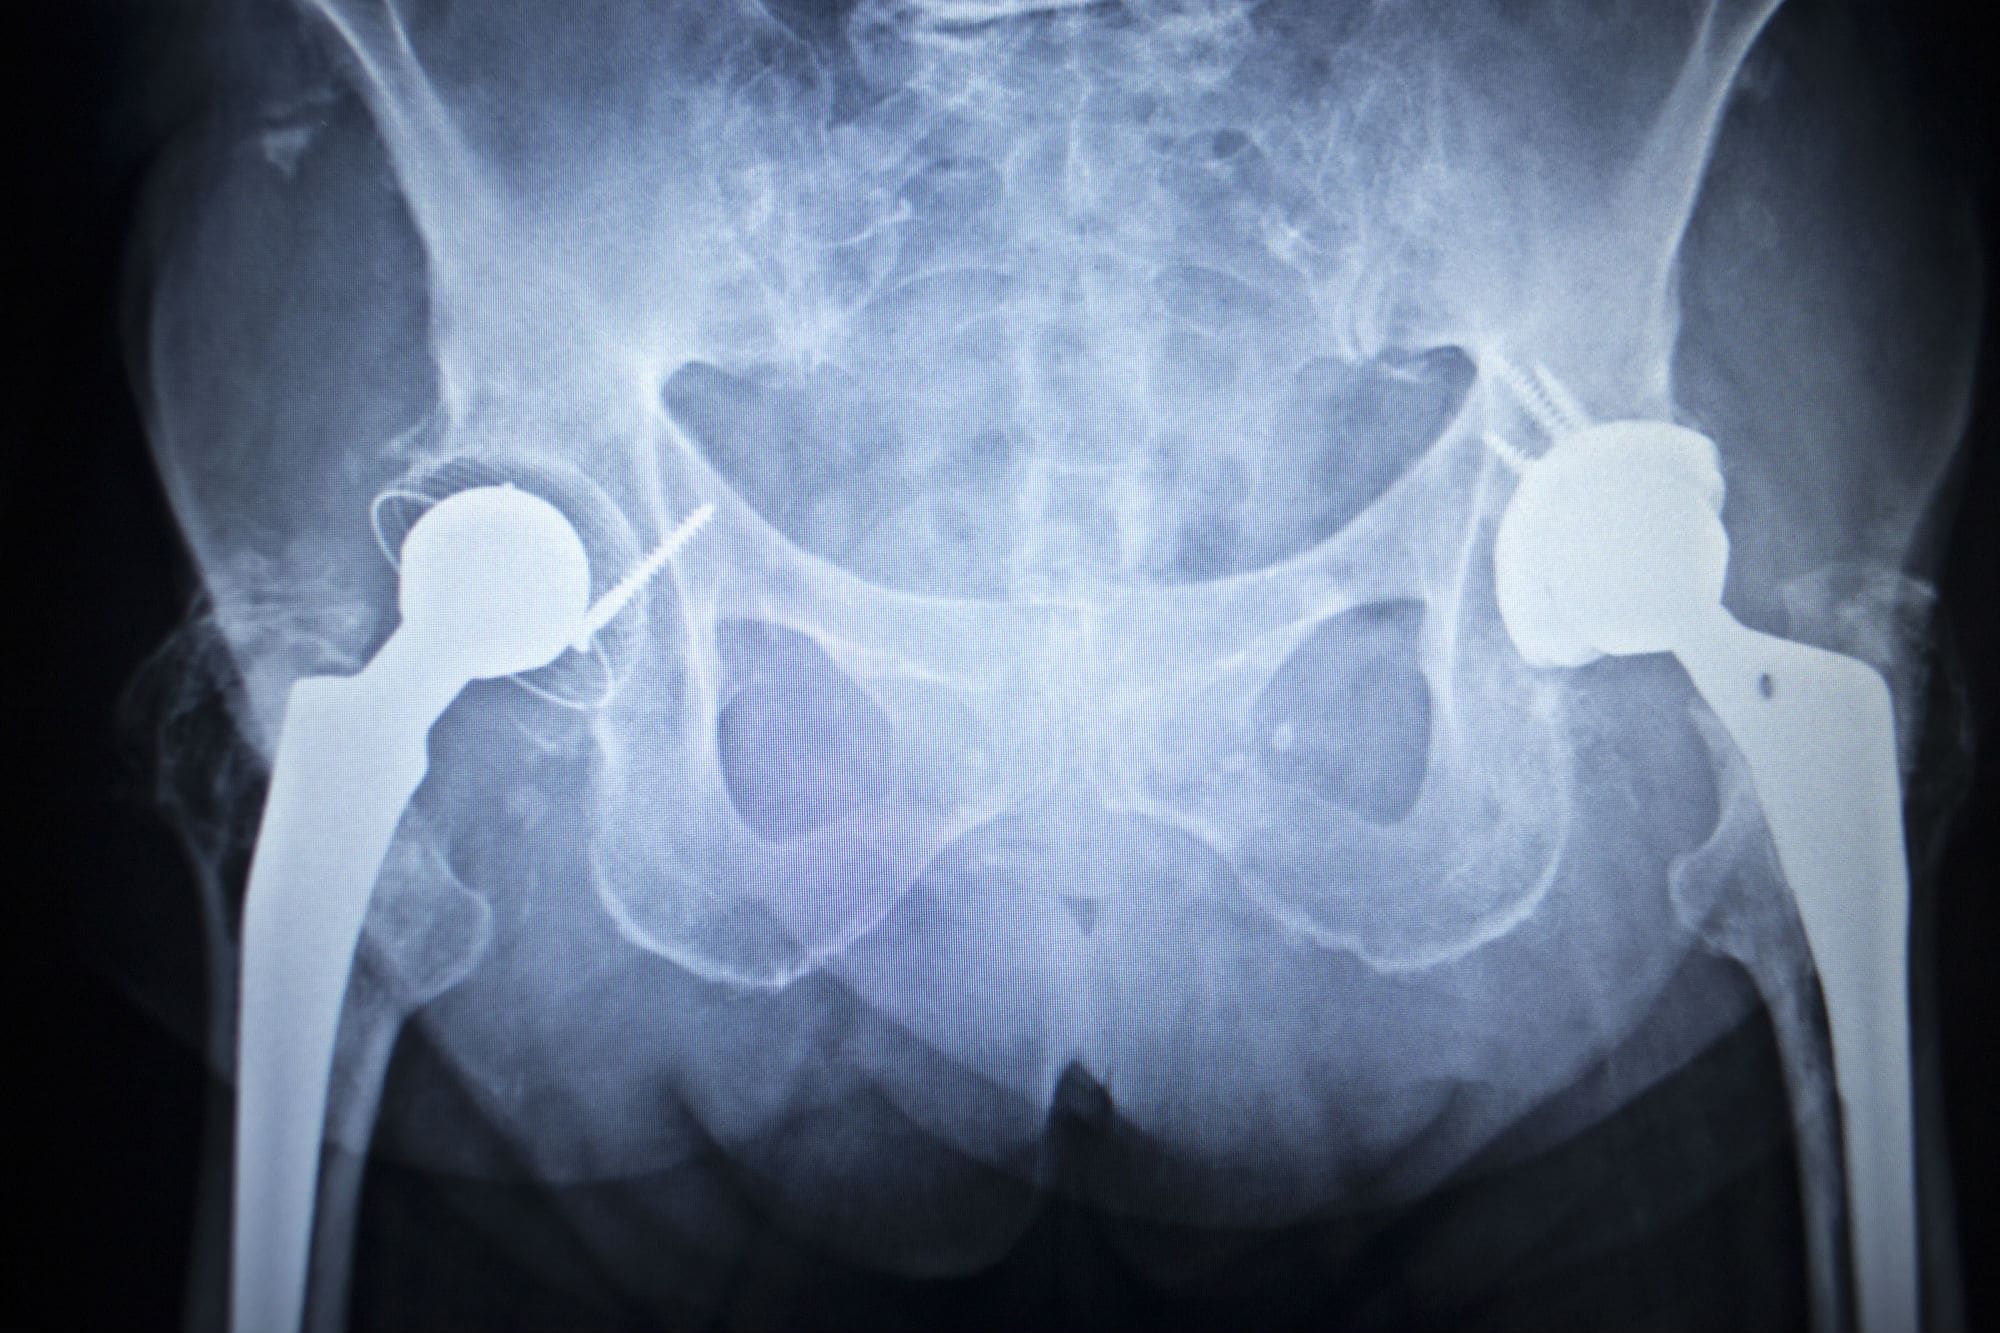

Zimmer Biomet Hip Replacement Lawsuit . Plaintiffs involved in the mdl have likely received their biomet hip replacement settlement. Zimmer biomet holdings has been sued over its faulty hip replacements in thousands of cases nationwide. Zimmer biomet hip replacement lawsuits claim the durom cup failed early, causing severe complications. There are currently 19 jury trials scheduled. The fda is getting the word out regarding a recall effort from zimmer biomet related to its discontinued cpt hip implant and. The defective medical device team of attorneys at weitz & luxenberg is inviting anyone who suffered a thigh fracture due to the. Mctlaw attorneys represent clients in lawsuits against zimmer biomet's metal on metal hip replacements. In july 2024, zimmer biomet issued a recall of their cpt hip system femoral stem 12/14 neck taper over concerns about the.

In july 2024, zimmer biomet issued a recall of their cpt hip system femoral stem 12/14 neck taper over concerns about the. Plaintiffs involved in the mdl have likely received their biomet hip replacement settlement. The defective medical device team of attorneys at weitz & luxenberg is inviting anyone who suffered a thigh fracture due to the. There are currently 19 jury trials scheduled. Mctlaw attorneys represent clients in lawsuits against zimmer biomet's metal on metal hip replacements. Zimmer biomet hip replacement lawsuits claim the durom cup failed early, causing severe complications. Zimmer biomet holdings has been sued over its faulty hip replacements in thousands of cases nationwide. The fda is getting the word out regarding a recall effort from zimmer biomet related to its discontinued cpt hip implant and.

Zimmer Biomet Hip Replacement Lawsuit There are currently 19 jury trials scheduled. Mctlaw attorneys represent clients in lawsuits against zimmer biomet's metal on metal hip replacements. Zimmer biomet holdings has been sued over its faulty hip replacements in thousands of cases nationwide. The defective medical device team of attorneys at weitz & luxenberg is inviting anyone who suffered a thigh fracture due to the. Plaintiffs involved in the mdl have likely received their biomet hip replacement settlement. Zimmer biomet hip replacement lawsuits claim the durom cup failed early, causing severe complications. There are currently 19 jury trials scheduled. In july 2024, zimmer biomet issued a recall of their cpt hip system femoral stem 12/14 neck taper over concerns about the. The fda is getting the word out regarding a recall effort from zimmer biomet related to its discontinued cpt hip implant and.